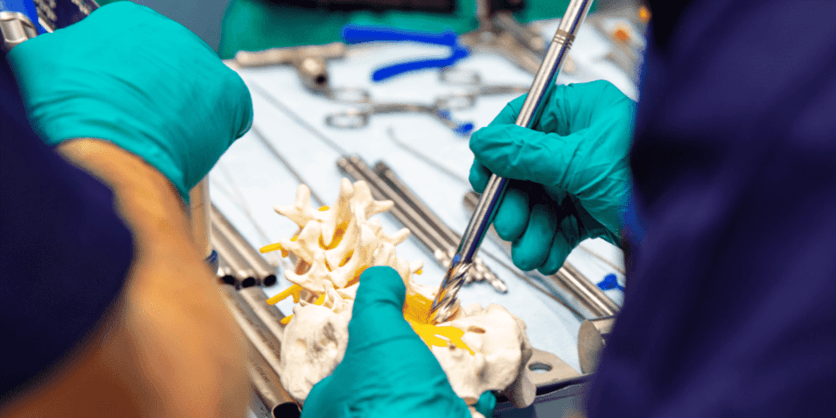

G21 is a forward-thinking Italian company specializing in advanced solutions for spinal surgery. They design high-quality implants and surgical instruments aimed at improving the outcomes of spinal procedures.

Their product range includes spinal implants for fusion and stabilization, along with minimally invasive tools that enable surgeons to perform precise and effective surgeries. Focused on enhancing patient recovery and reducing surgery times, G21 is dedicated to providing reliable, innovative technologies for better results and faster healing.Products